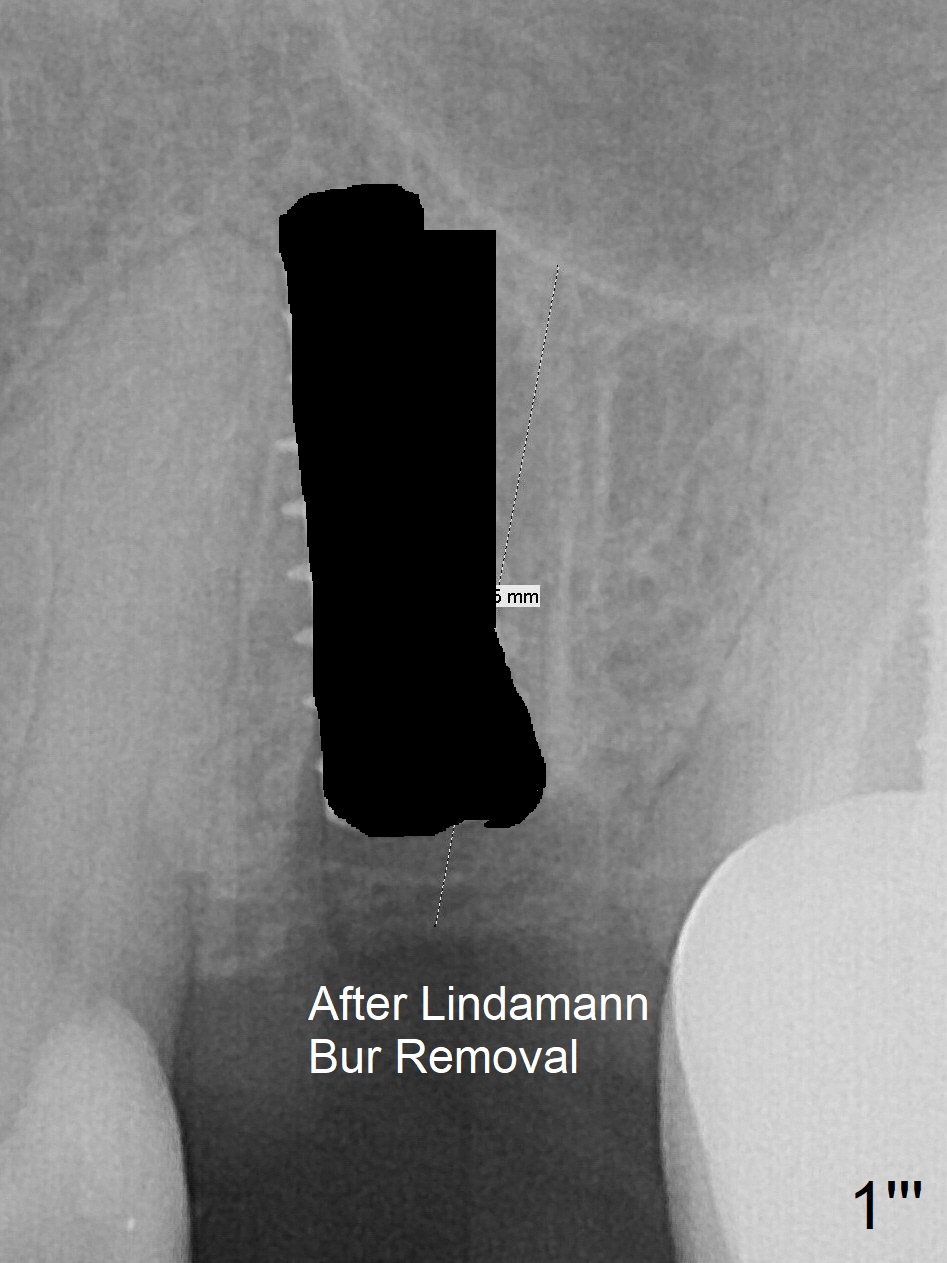

First, the implant is removed (Fig1'). Move the osteotomy distal by using Lindamann bur (Fig.1''). Remove the Lindamann bur (Fig.1'''). Reuse 3.3 m Magic Drill (Fig.1''''). After using Lindamann bur to move the osteotomy distal and reusing 3.3 mm drill, the trajectory of a 4.5x11 mm IBS dummy implant improves (Fig.2 with low stability).